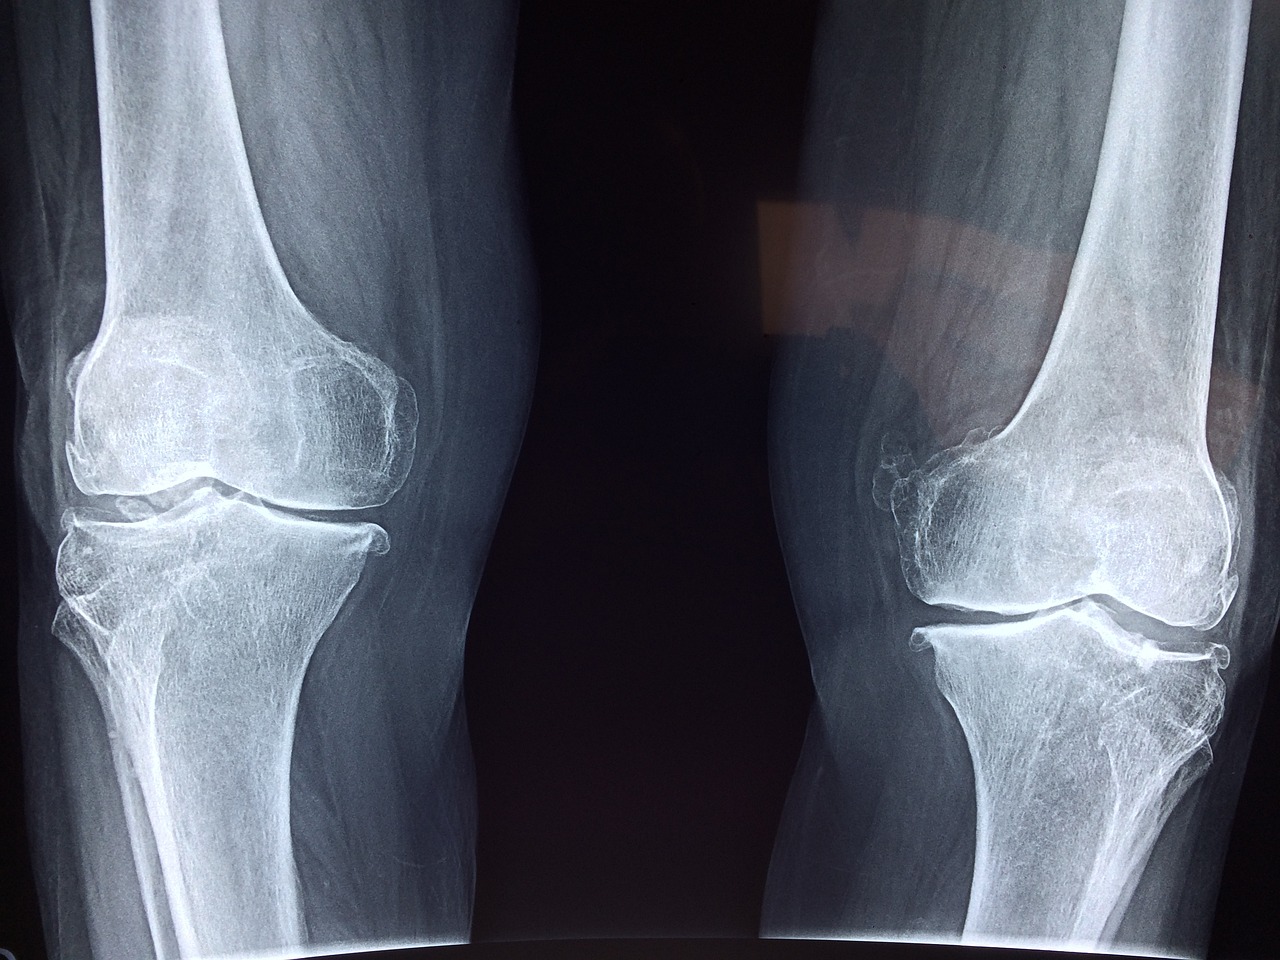

특히 연골이 닳기 시작한 50대 이상이나 퇴행성관절염 초기 증상이 있는 분들에게는 무릎에 체중이 실리는 동작은 오히려 부담이 될 수 있습니다.